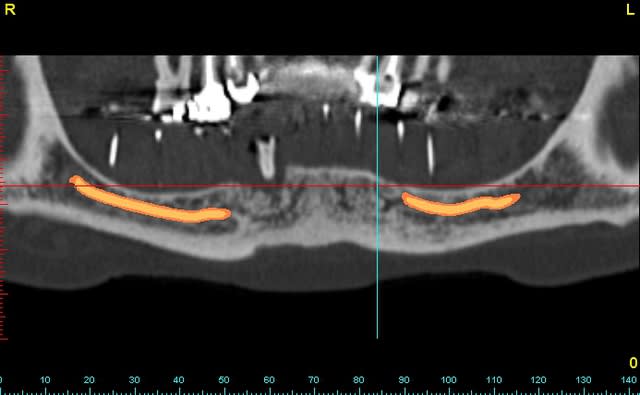

pano 5 et photo 6 ce matin